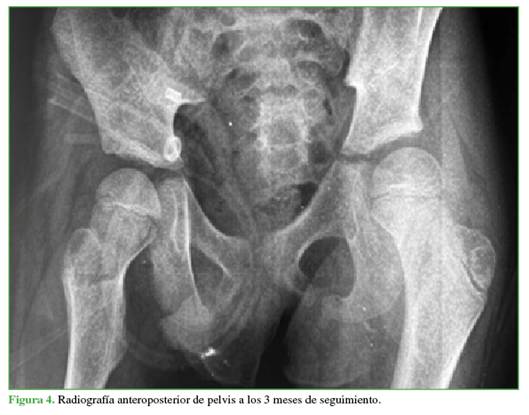

Se realizó una intubación orotraqueal. La TC de cráneo mostró un hematoma epidural y una fractura frontotemporal sin criterios quirúrgicos. En primera instancia, la TC de pelvis reveló una incongruencia articular coxofemoral derecha, caracterizada por una luxación anterior en presentación obturadora (Figura 2), se descartaron lesiones asociadas.

En las radiografías de control a los 3 (Figura 4) y 6 meses (Figura 5), no se visualizaron hallazgos de NAV y también se descartaron otras complicaciones osteomusculares asociadas a la luxación traumática.